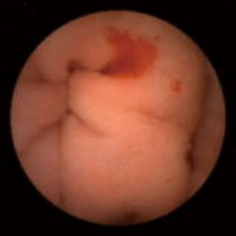

早期胃癌に対するESD

1.胃の幽門部のほとんどを占める早期胃癌。FICE(FUJI intelligent Chromo Endoscopy)・BLI(Blue LASER Imaging)を用いて病変の性質と境界を診断していきます。

2.当科が開発した先端細径透明フード(STフード)とヒアルロン酸ナトリウム局注液を使用して、内視鏡下に電気メスで病変を剥離していきます。

3.病変を取り去ったあとの胃と切除標本。胃の出口付近の粘膜のほとんどを剥離しました。